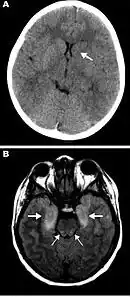

| a-b)Magnetic resonance images and computed tomography neuroradiographs showing lesions in brains of children with eastern equine encephalitis | |